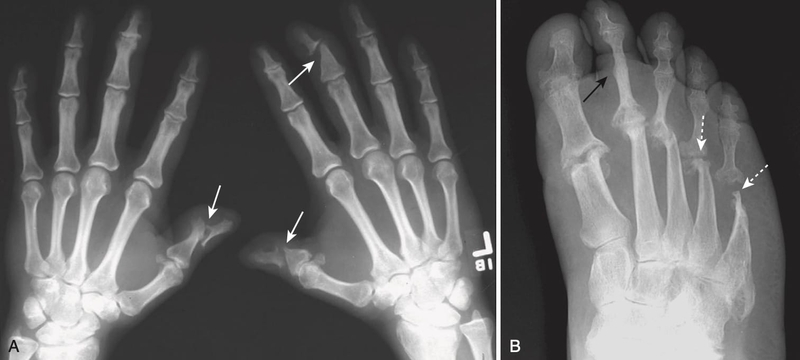

Trong một số trường hợp, đặc biệt là khi bệnh nhân có các biểu hiện liên quan đến khớp, bác sĩ có thể chỉ định các phương pháp xét nghiệm hình ảnh như X-quang, MRI (Magnetic Resonance Imaging), hoặc siêu âm để đánh giá mức độ ảnh hưởng của vảy nến đến khớp. Các phương pháp này giúp bác sĩ xác định sự tồn tại của viêm khớp vảy nến và đề xuất liệu pháp điều trị phù hợp.